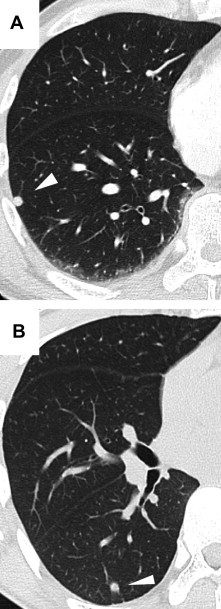

We encountered nine cases of IPLNs, discovered by chest radiography or chest CT (Fig. 1). The clinical data of the patients with IPLNs are summarized in Table 1. All the patients were Japanese. They included nine males and two females, and their ages ranged from 38 to 73 years, with a mean of 60.0 years. All the male IPLN patients were heavy smokers (Brinkman index >400). Three patients had a past history of malignancy and had inhaled dust at their place of work. The thin-section CT findings of IPLNs are summarized in Table 2. In all cases of IPLNs, nodules were located in the lower lobe. They did not have calcification. Their sizes ranged from 4 to 8 mm (mean, 6.2 mm). In five and four cases, nodules were located in the right and left lobes, respectively. Three cases had progression of their nodule size for a mean follow-up period of 3.7 months and two cases had multiple nodules. The distance from the pleura ranged from 0 to 18 mm (mean, 3 mm). In six cases, the nodules were round, and linear density extending from the IPLNs was visualized in seven nodules. Neither enhancement in contrast nor pleural indentation was detected in the IPLNs.

(A) Chest computed tomography revealed a small, round nodule in the lower lobe ...

Figure 1.

(A) Chest computed tomography revealed a small, round nodule in the lower lobe (case 2). (B) An angular and partly spiculated nodule shown in the lower lobe (case 5).